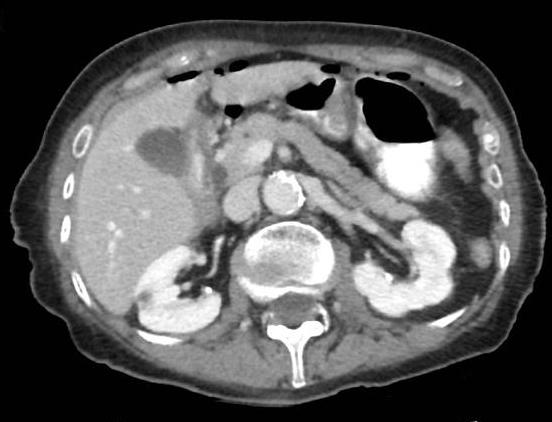

Image radiologique TDM normale de l'intestin :

Il y avait la difference de

image de intestin grele avec gros intestin ( colon )

en coupe TDM axiale . Intestin grele sont en pleine

du contenue , avec plusieure des plies muqueuse . La

colon avait moindre de plie muqueuse et sa diametre est grande et parfois presente

de poche a air . |